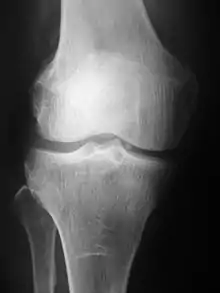

Radiography of the knee using a DR machine

Radiographs (originally called roentgenographs, named after the discoverer of X-rays, Wilhelm Conrad Röntgen) are produced by transmitting X-rays through a patient. The X-rays are projected through the body onto a detector; an image is formed based on which rays pass through (and are detected) versus those that are absorbed or scattered in the patient (and thus are not detected). Röntgen discovered X-rays on November 8, 1895, and received the first Nobel Prize in Physics for his discovery in 1901.

Plain radiography was the only imaging modality available during the first 50 years of radiology. Due to its availability, speed, and lower costs compared to other modalities, radiography is often the first-line test of choice in radiologic diagnosis. Also despite the large amount of data in CT scans, MR scans and other digital-based imaging, there are many disease entities in which the classic diagnosis is obtained by plain radiographs. Examples include various types of arthritis and pneumonia, bone tumors (especially benign bone tumors), fractures, congenital skeletal anomalies, and certain kidney stones.